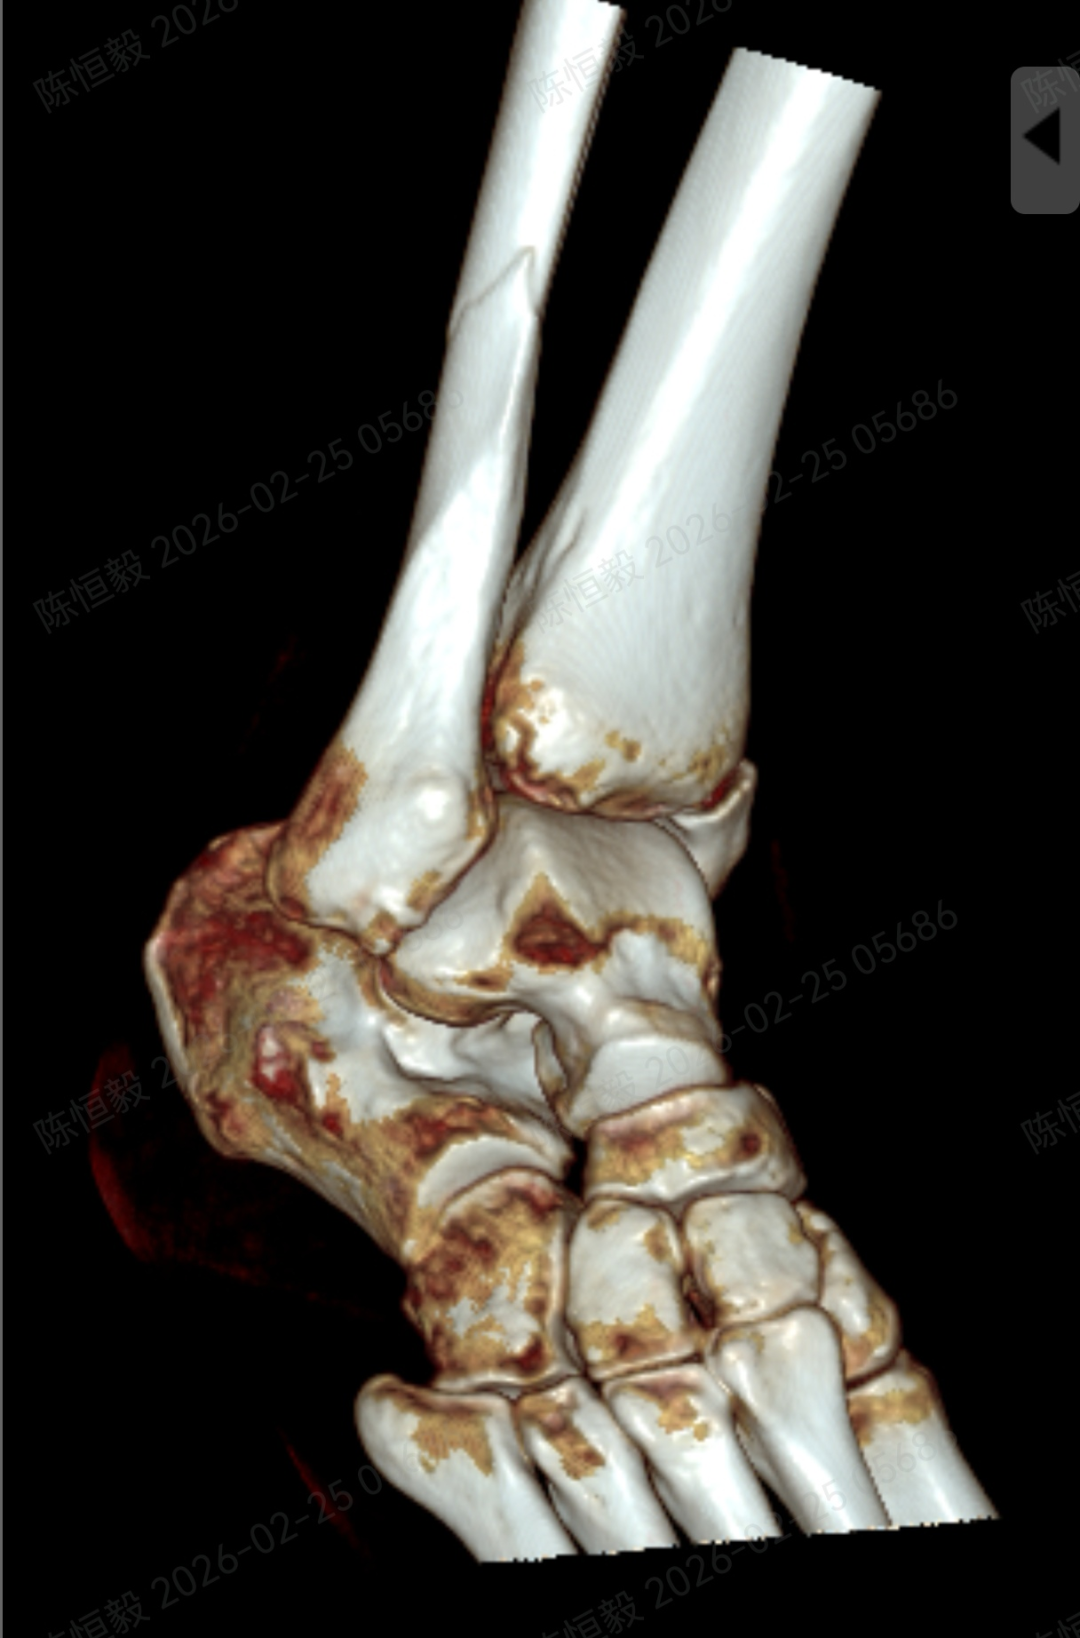

针对王女士的踝关节骨折情况,由副主任医师陈涛主刀,足踝外科团队为其实施了关节镜辅助下机器人导航微创闭合复位内固定术。

通过 5 毫米小切口将关节镜探入关节腔内,清理腔内淤血与致炎因子,清晰观察骨折块移位及关节软骨损伤情况;

在关节镜直视下,使用微创器械将骨折块复位至解剖位置,恢复关节面平整;

依托机器人导航系统,规划螺钉置入通道,避开关节面与重要组织;

最后通过另外两个 5 毫米的小孔置入空心螺钉,完成骨折端的稳定固定。

整个手术仅通过三个 5 毫米的小切口完成,最大程度降低了手术创伤。

本次诊疗中,在关节镜直视下确保骨折部位实现解剖复位,同时对检查中发现的合并软骨损伤进行了同步处理,为关节的后续恢复提供了保障。